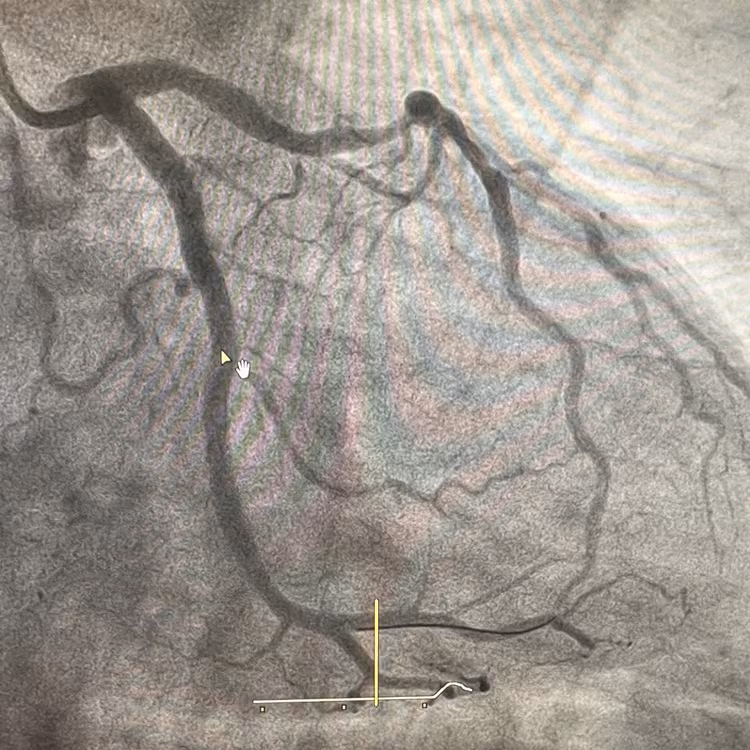

Qua thăm khám và thực hiện chụp mạch vành qua da, bác sĩ xác định bệnh nhân bị tổn thương nặng cả 3 thân động mạch vành, trong đó nhánh LCx là "thủ phạm" chính gây nhồi máu cơ tim cấp trong đợt này.

Quy trình nong bóng và đặt Stent phủ đã được tiến hành khẩn trương và chính xác, giúp mở lại dòng máu qua nhánh LCx, khôi phục sự tưới máu cho tim. Stent được đặt thành công, bao phủ toàn bộ vùng tổn thương, đảm bảo tối ưu hiệu quả điều trị.